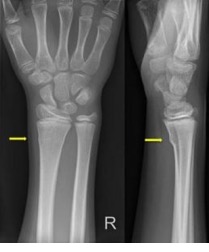

Uw kind heeft een kleine breuk in de ellepijp of het spaakbeen, in de buurt van de pols. Het is een knikje in het bot. Dit heet een Torus fractuur. Als behandeling krijgt uw kind een tubigrip en een sling. Een sling is een soort mitella.

Deze breuk komt vaak voor bij kinderen. De behandeling is een tubigrip en een sling. Een sling is een soort mitella.